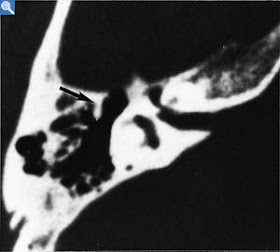

inner ear malformation computed tomographyCoronal section through the middle ear at the level of the oval window niche. Isolated malformation with a dilated lateral semicircular canal (arrow). The second portion of the facial nerve canal runs in a normal fashion underneath the lateral semicircular canal (crossed arrow).